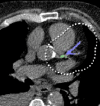

Almost 35 years after its introduction, coronary artery calcium score (CACS) not only survived technological advances but became one of the cornerstones of contemporary cardiovascular imaging. Its simplicity and quantitative nature established it as one of the most robust approaches for atherosclerotic cardiovascular disease risk stratification in primary prevention and a powerful tool to guide therapeutic choices. Groundbreaking advances in computational models and computer power translated into a surge of artificial intelligence (AI)-based approaches directly or indirectly linked to CACS analysis. This review aims to provide essential knowledge on the AI-based techniques currently applied to CACS, setting the stage for a holistic analysis of the use of these techniques in coronary artery calcium imaging. While the focus of the review will be detailing the evidence, strengths, and limitations of end-to-end CACS algorithms in electrocardiography-gated and non-gated scans, the current role of deep-learning image reconstructions, segmentation techniques, and combined applications such as simultaneous coronary artery calcium and pulmonary nodule segmentation, will also be discussed.